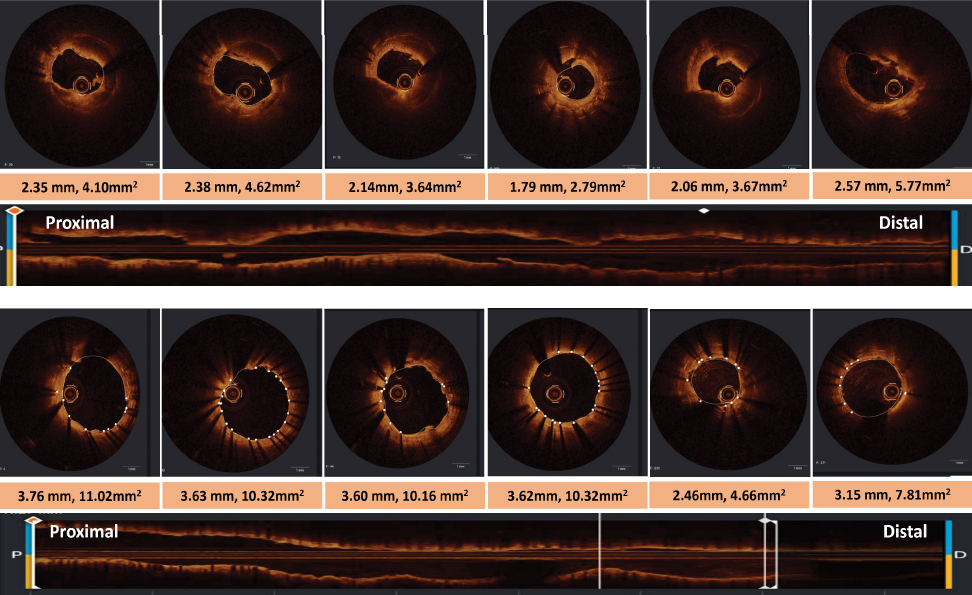

The

final OCT confirmed TIMI-3 flow and a significant increase in the minimum lumen

area from 2.79 to 7.81 mm² (Fig. 2).

Figure

2. OCT images acquired after

Penumbra-guided thromboaspiration (upper panel) and final OCT images

following stent placement (lower panel).